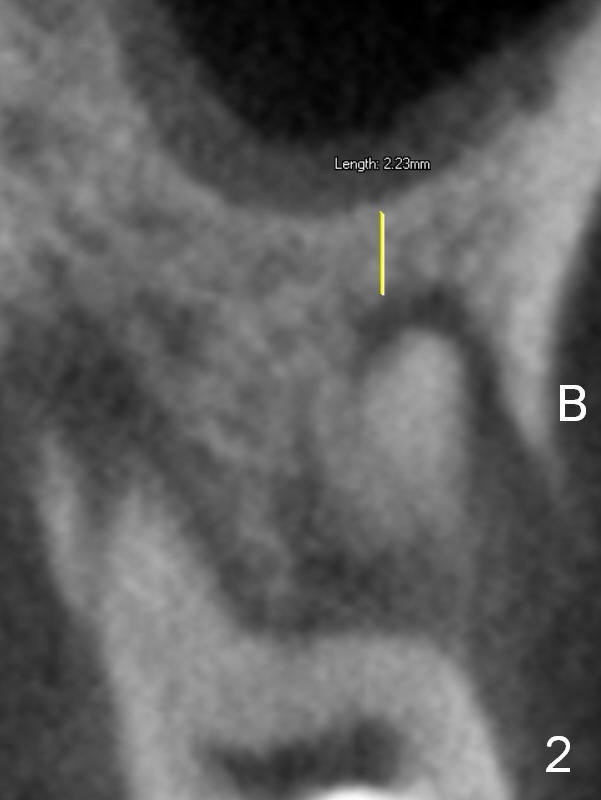

Preop CT shows that the septum appears to be able to hold a 11 mm long implant (Fig.1 sagittal section). There are periapical radiolucent lesions of the buccal (Fig.2 (coronal section) B) and palatal roots; bone height above the buccal apex is ~ 2 mm (Fig.3). When the tooth #14 is extracted, a 1.6 mm pilot drill is used to start osteotomy in the middle of the fairly thin septum (Fig.3 red line, Fig.4 S). It is hoped that Magic Expanders (ME) can enlarge the osteotomy by pushing the buccal and palatal bone plates of the septum outward (Fig.5 arrows).